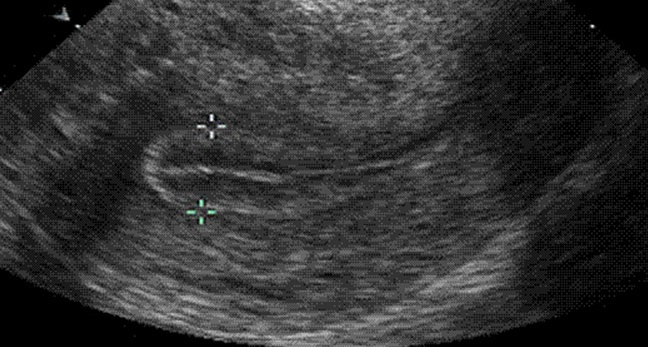

三线征中的“三线”指的是,子宫内膜与子宫肌层之间形成的上下两条高回声的外侧线,及两层子宫内膜表层紧贴形成的清晰可见的一条高回声的中心线。三线征是超声下子宫内膜形态的一种描述,反应的是子宫内膜不同时期的不同形态。

形态描述:典型三线征,子宫内膜的三条线非常清晰,呈“嘴唇样”,外层和中央为强回声线,外层和宫腔中线间为低回声区或暗区。这种内膜非常有利于胚胎着床和生长。

形态描述:仍可见三线征,但子宫肌层与内膜基底层交界处强回声增厚,变模糊,而中央宫腔线回声变低,稍模糊,两者之间的回声仍为相对较低回声区。

移植前进行B超检查,如果三线清晰,说明子宫内膜形态发育良好,适合胚胎着床;如果三线征不明显或没有出现,内膜回声紊乱,则可能是子宫内膜异常或内分泌紊乱。当然在辅助生殖过程中,北京家恩德运医院的医生认为大家更需要关注的是子宫内膜的厚度变化, 7mm是移植时子宫内膜厚度的最低要求,最好范围是在8-12mm之间,如果内膜厚度达到9mm及以上,移植后可获得理想的妊娠率。